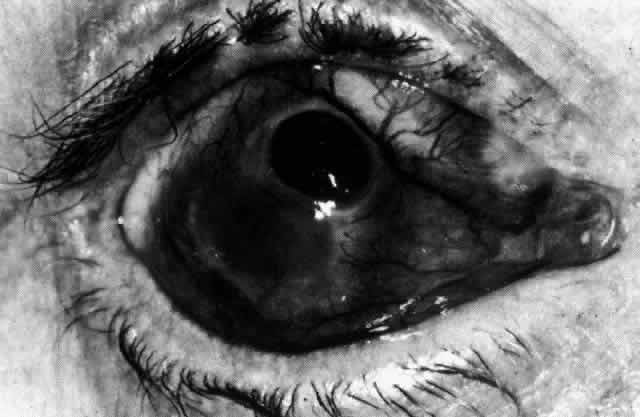

Diffuse Anterior Scleritis Diffuse anterior scleritis is the most common and least severe type of scleritis. The inflammation is widespread, and it may involve either a small segment or the whole of the anterior segment, sometimes with such severe overlying inflammation as to justify the name “brawny” scleritis (Fig. 29). On slit lamp examination, the vascular pattern of both deep and superficial layers may be distorted, so that the normal radial pattern of the vessels is lost; large anastomotic channels develop, leading to beading and tortuosity of the remaining vessels (Figs. 30 and 31; Color Plate 1C).

In this relatively benign form of scleral inflammation, the fluorescein angiogram reveals a rapid flow pattern in which the transit time of the dye is very rapid (as in episcleritis) (Figs. 32 and 33). Subtle changes occur in the capillary network, and abnormal leaking vessels appear after prolonged inflammation. These changes do not disappear after the inflammation subsides or is treated (see Fig. 31).